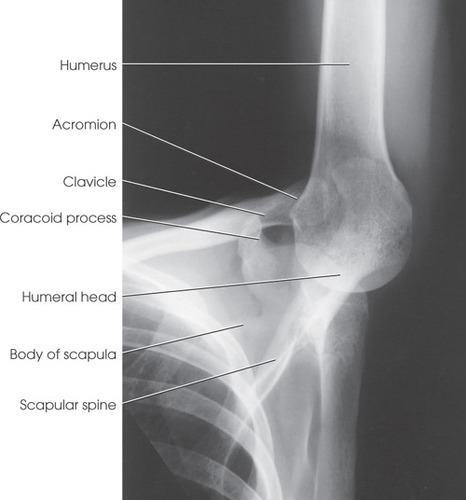

1. 견관절 전방탈구에 의한 Humeral Head의 후측방의 골결손(hill-Sachs lesion)

2. Humeral Head의 후측방 상의 압박골절

3. Humeral Head의 탈골

1. humeral Head의 후측방 사진의 Fracture확인

2. Hill- Sachs Lesion